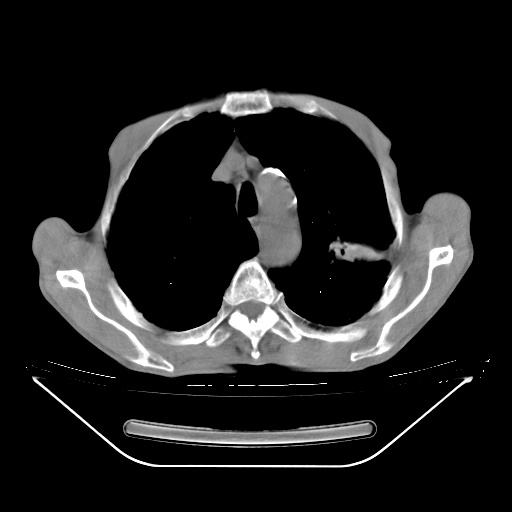

以下是引用zsl6918在2008-8-25 21:55:00的发言:[br]符合右肺周围性肺癌并肺内转移,左肺结核球。双肺肺气肿。腰椎附件转移。

以下是引用随光逐影在2008-8-25 22:03:00的发言:[br]1)考虑右肺下叶周围性肺癌并肺内转移,腰椎附件转移。2)左上肺结核(结核球形成)。3)双肺肺气肿(多发肺大泡形成)。4)双肺门区及纵隔内多发淋巴结钙化。